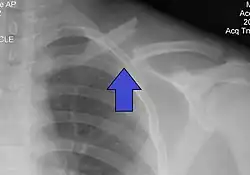

It is often caused by a fall onto a shoulder, outstretched arm, or direct trauma.[1][3] The fracture can also occur in a baby during childbirth.[1] The middle section of the clavicle is most often involved.[3] Diagnosis is typically based on symptoms and confirmed with X-rays.[2]

The basic method to check for a clavicle fracture is by an X-ray of the clavicle to determine the fracture type and extent of injury. In former times, X-rays were taken of both clavicle bones for comparison purposes. Due to the curved shape in a tilted plane X-rays are typically oriented with ~15° upwards facing tilt from the front. In more severe cases, a computerized tomography (CT) or magnetic resonance imaging (MRI) scan is taken. However, the standard method of diagnosis through ultrasound imaging performed in the emergency room may be equally accurate in children.[5]